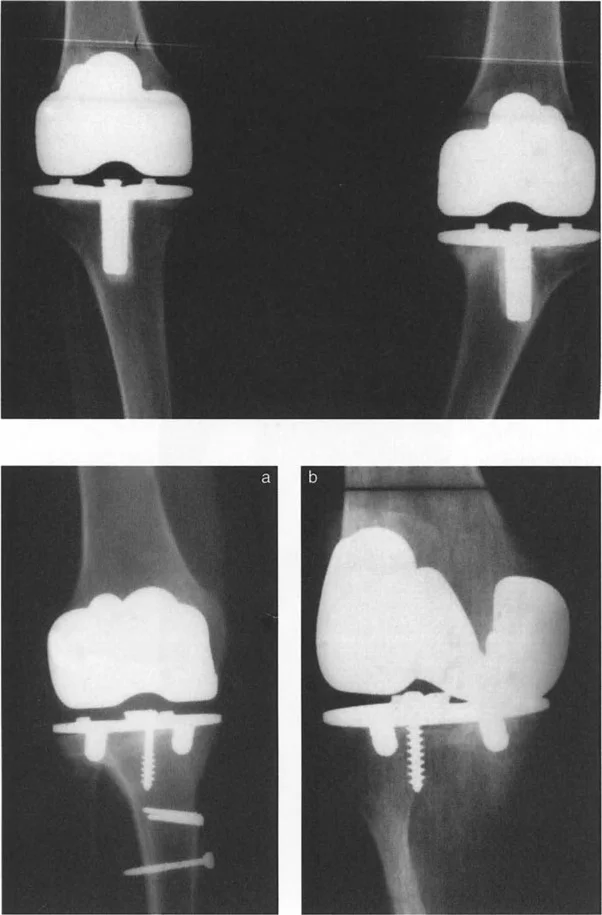

- استبدال المفاصل في حالات التشوه الشديد

في حين أن التشوهات الديناميكية تُناقش غالبًا في سياق أمراض الأعصاب والعضلات لدى الأطفال، فإن المبادئ البيوميكانيكية التي تحكمها تنطبق عالميًا على إعادة بناء العظام لدى البالغين. يشمل ذلك سيناريوهات إعادة البناء المعقدة للغاية، مثل استبدال مفصل الركبة الكلي (TKR) واستبدال مفصل الورك الكلي (THR) المرتبطة بالانحرافات الشديدة خارج المفصل. إن فهم الأذرع الرافعة هو المتطلب الأساسي لإتقان هذه التقنيات المتقدمة في جراحة المفاصل وقطع العظم، وهو ما يتقنه الأستاذ الدكتور محمد هطيف في ممارسته اليومية.

تُعد الأشعة السينية والتصوير المقطعي المحوسب والرنين المغناطيسي أدوات حاسمة لتحديد التشوهات الهيكلية وتقييم المحاور الميكانيكية.

- الأشعة السينية (X-rays):

- الأشعة الثابتة: تُستخدم لتقييم التشوهات العظمية الواضحة، والتئام الكسور، وحالة المفاصل.

- الأشعة مع تحمل الوزن (Weight-bearing X-rays): تُظهر كيف تتصرف المفاصل والعظام تحت الضغط الطبيعي للجسم، وهو أمر حيوي لتقييم التشوهات الديناميكية.

- أشعة الأطراف الطويلة (Long Leg Films): تُؤخذ هذه الأشعة من الورك إلى الكاحل في صورة واحدة لتقييم المحور الميكانيكي الكامل للطرف السفلي وتحديد أي انحرافات.